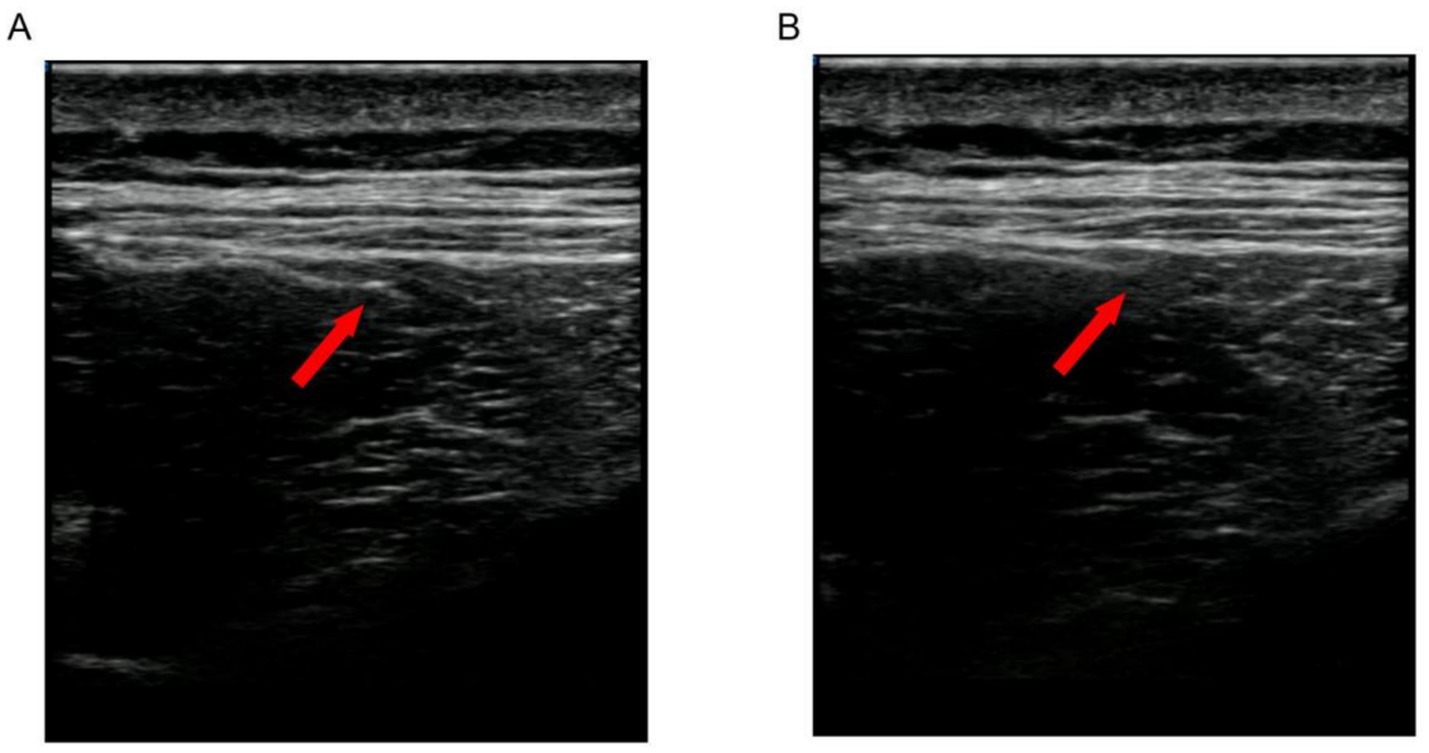

In Group B (the ultrasound-guided acupotomy group), (1) the patient was placed in a prone position, with the treatment area fully exposed; the doctor was located on the patient’s side; and the ultrasound instrument was placed in front of the doctor. (2) Palpation and localization: The lumbar erector spinae and multifidus muscles were palpated and localized by the same experienced clinician, and each subject was palpated bilaterally next to the spinous processes of the lumbar vertebrae L3 and L5. When pressure points and mass-like painful hard nodules or striated muscle fiber spasm bands were palpated, MTrPs were marked with a pen at the site. (3) Disinfection: A 15-cm area centered on the fixation point was disinfected with iodine volts 2 times, after which a sterile cavity towel was spread out. (4) Ultrasound-guided acupotomy manipulation: A SONI MAGE HS1 color ultrasonography diagnostic instrument was used with an ultrasound probe model number of L11-3, and longitudinal cuts and transverse cuts were made along the lumbar erector spinae muscle fibers, and the lumbar spine muscle fibers were cut longitudinally and transversally. Longitudinal and transverse scans were performed along the lumbar erector spinae muscle fibers to confirm the extent of the erector spinae and multifidus muscles as well as the lumbar spinous processes and articular syndromes and to search for MTrPs. Normal muscle fibers were hypoechoic under ultrasound imaging, and MTrPs were oval shaped, locally heterogeneous and hyperechoic areas. Under ultrasound guidance, the acupotomy (0.6 × 50 mm, Beijing Huaxia Acupotomy Medical Instrument Factory) was inserted into the muscle tissue with the knife line parallel to the longitudinal axis of the torso and the body of the acupotomy perpendicular to the ketosis body, and two to three cuts were made into each area until the abnormal echoes in that area were not visible (Figure 1). If there are multiple MTrPs, the above treatment should be repeated. (5) Postoperative treatment: Pressure was applied to stop the bleeding, and a band aid was applied. Treatments were performed once a week for 15 min, three times per course of treatment, for a total of 3 weeks.

Figure 1. Two-dimensional ultrasonography images from the same patient before and after treatment. The red arrow: myofascial trigger points (MTrPs). (A) MTrPs showing oval, locally heterogeneous hyper echoic areas in two-dimensional ultrasound observation. (B) After repeated puncture of the MTrPs with a dry needle, the localized echoes diminished. With a dry needle, the localized echoes diminished, and the entangled muscles unraveled and relaxed.